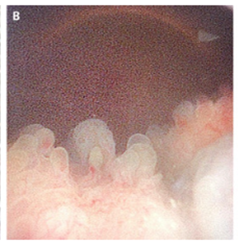

膀胱鏡検査施行。ポリープ状の塊が膀胱内腔に押し出ていることが示唆された。

膀胱生検も施行され、多数の住血吸虫卵、急性および慢性の乳頭状膀胱炎およびポリープ状膀胱炎が認められ、異形成は認められなかった。